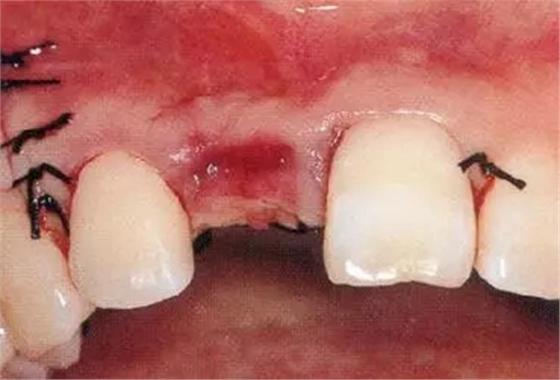

▲圖44-12,13

圖44-12 種植體植入4個月后。二次手術(shù)時同時進行結(jié)締組織移植(CTG),以增大牙齦。

圖44-13 二次手術(shù)后的狀態(tài)。

圖44-14

同時期的X光片。